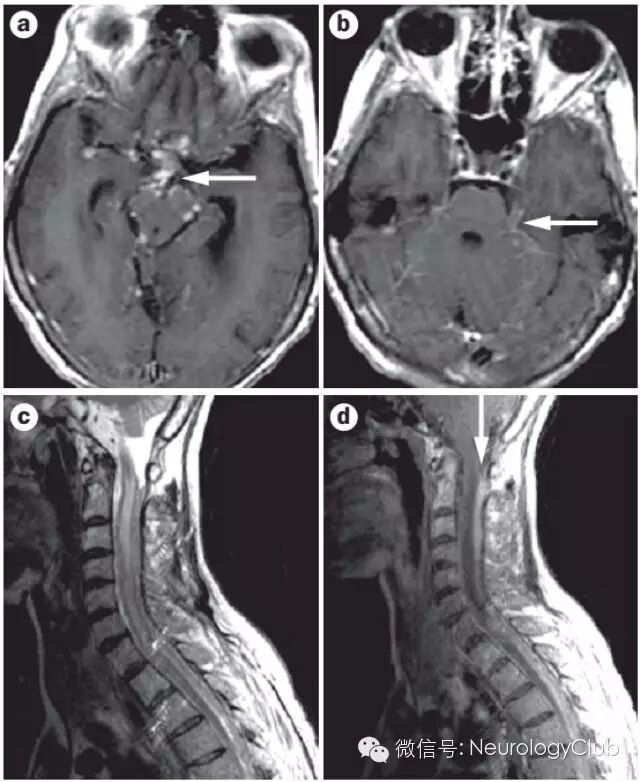

2急性播散性脑脊髓炎

(A:矢状位T2WI提示急性期脊髓长节段T2高信号;B:3月后复查病灶明显消失;C:冠状位FLAIR提示脑室旁,皮质下白质以及基底节区多发T2高信号;D:3月后复查病灶明显消失)

3干燥综合征

(a:C2-T2脊髓长节段T2高信号病灶;b:3天后复查;c:2周后复查;d:1.5年后复查,可见进行性脊髓萎缩)